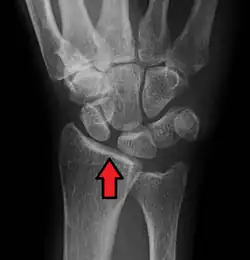

X-ray images indicate scapholunate ligament instability when the scapholunate distance is more than 3 mm, which is called scapholunate dissociation.[7] A static scapholunate instability is generally readily visible, but a dynamic scapholunate instability can only be seen radiographically in certain wrist positions or under certain loading conditions, such as when clenching the wrist, or loading the wrist in ulnar deviation.[6]

In order to diagnose a SLAC wrist you need a posterior anterior (PA) view X-ray, a lateral view X-ray and a fist view X-ray.[8] The fist X-ray is often made if there is no convincing Terry Thomas sign. A fist X-ray of a scapholunate ligament rupture will show a descending capitate bone. Making a fist will give pressure at the capitate, which will descend if there is a rupture in the scapholunate ligament.

Static scapholunate dissociation -

Scapholunate ligament disruption associated with a Colles' fracture